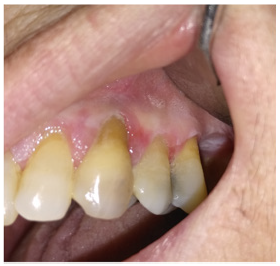

A 58 years old female patient, with a previous diagnosis of oral lichen planus went to my private practice for a follow up visit. The medical anamnesis was positive for hysterectomy about 30 years ago, arthrosis, mild hypertension, gastro-esophageal reflux. A new asymptomatic lesion between the gingival papilla of the element 24 and 25 was present. It is an exophytic pink-white lesion, of irregular shape, of about 0,5 cm, near gingival lesion already present due to the oral lichen planus. The patient did not want to perform a histological examination in that day because she had an important event the day after. I have decided to treat the region between the gum around the element 24 and 25 with a session of photodynamic therapy (PDT). PDT was performed with a 630 nm LED red light (FotoSan 630, CMD Dental, Cophenagen, Denmark) in combination with Toluidine Blue (0,1 mg/ml). The lights applied have very mild affinity with mammalian cells.

For this there are no adverse effects during the treatments. The intensity of the light that emitted diodes is between 2000 and 4000MW/cm2. This device works with three different modalities that correspond to different time cycles of application: 10, 20, and 30 seconds, respectively. The dye was applied on the entire surface of the lesion beyond the margins and even encroaching on healthy tissue. The light diode was then turned on with a wavelength of 630 nm with 5 cycles of 30 seconds. a long-pipped tip was used and circular movements of about 0.5 cm above it were performed. At the end of the 5 applications, the dye was completely removed with a gauze and the patient performed a final rinsing with water. One week later, the exophytic lesion was reduced, of about 0,3 mm and hade a regular shape. The gingival tissue around the element 24 returned pink (Figures 1 & 2). I have decided to remove the exophytic lesion with a biopsy for an histological examination, that confirmed the diagnosis of squamous papilloma from HPV infection. After one week, at the follow up visit the tissues healed (Figure 3). I have informed the patient about the risk connected with the development of oral cancer in patient with oral lichen planus and HPV lesions.